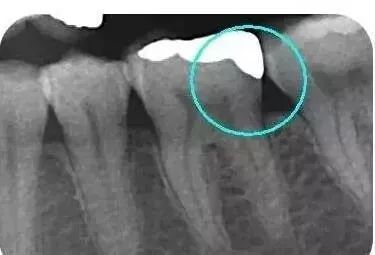

從下面這張x線片中可以看出,嵌體遠(yuǎn)中與牙體邊緣密合相接無懸突。

這樣的嵌體在戴到患者口內(nèi)的時(shí)候,是比較適合的,堅(jiān)固耐用且不會(huì)有不適的感覺。